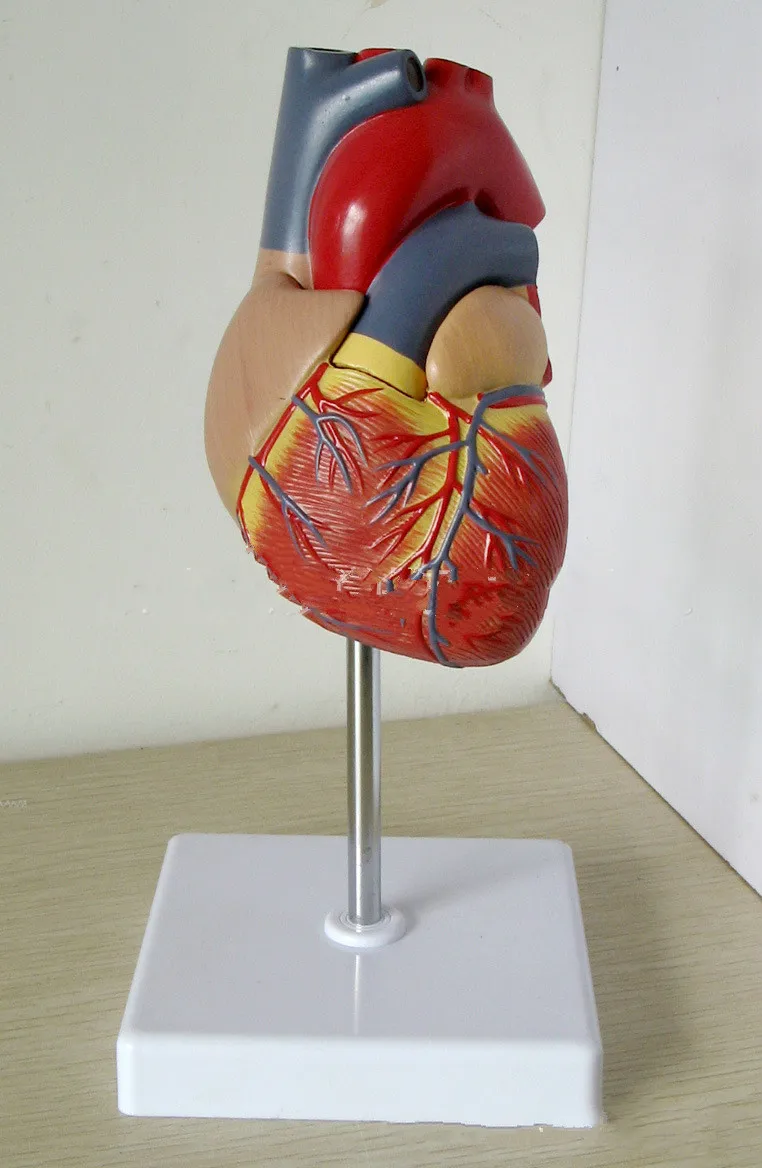

Фотографии и 3D-модели анатомии сердца человека